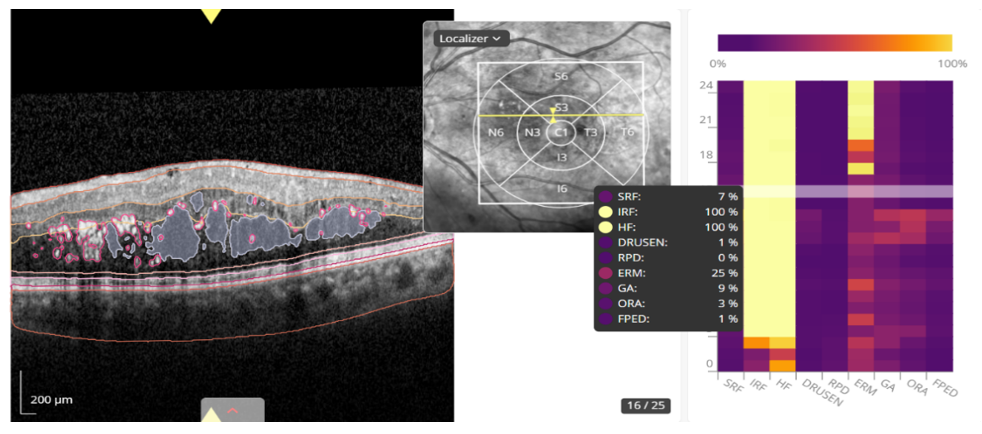

OCT scans were performed with the Heidelberg tomograph (Spectralis, Heidelberg, Germany) and analyzed using the AI Discovery 4.4 platform (RetinAI, Switzerland) for quantification of retinal biomarkers, focusing on the central OCT scan areas of 1 mm, 6 mm and total macular cube (Figure 1). Data included tomographic variables such as subretinal fluid (SRF), intraretinal fluid (IRF) and pigment epithelial detachment (PED), measured in nanoliters. Biomarkers included SRF, IRF, HF, drusen, reticular pseudodrusen (RPD), epiretinal membrane (ERM), geographic atrophy (GA) and outer retinal atrophy (ORA). A biomarker was considered to be present if its probability of being found by AI was equal to or greater than 90%. Unless otherwise specified, quantitative thickness values correspond to the central 1-mm ETDRS subfield.

Figure 1 OCT analysis interface using AI (Discovery 4.4) of a patient with DMO. On the right, the different probabilities of presence of each biomarker given by the AI system are shown.